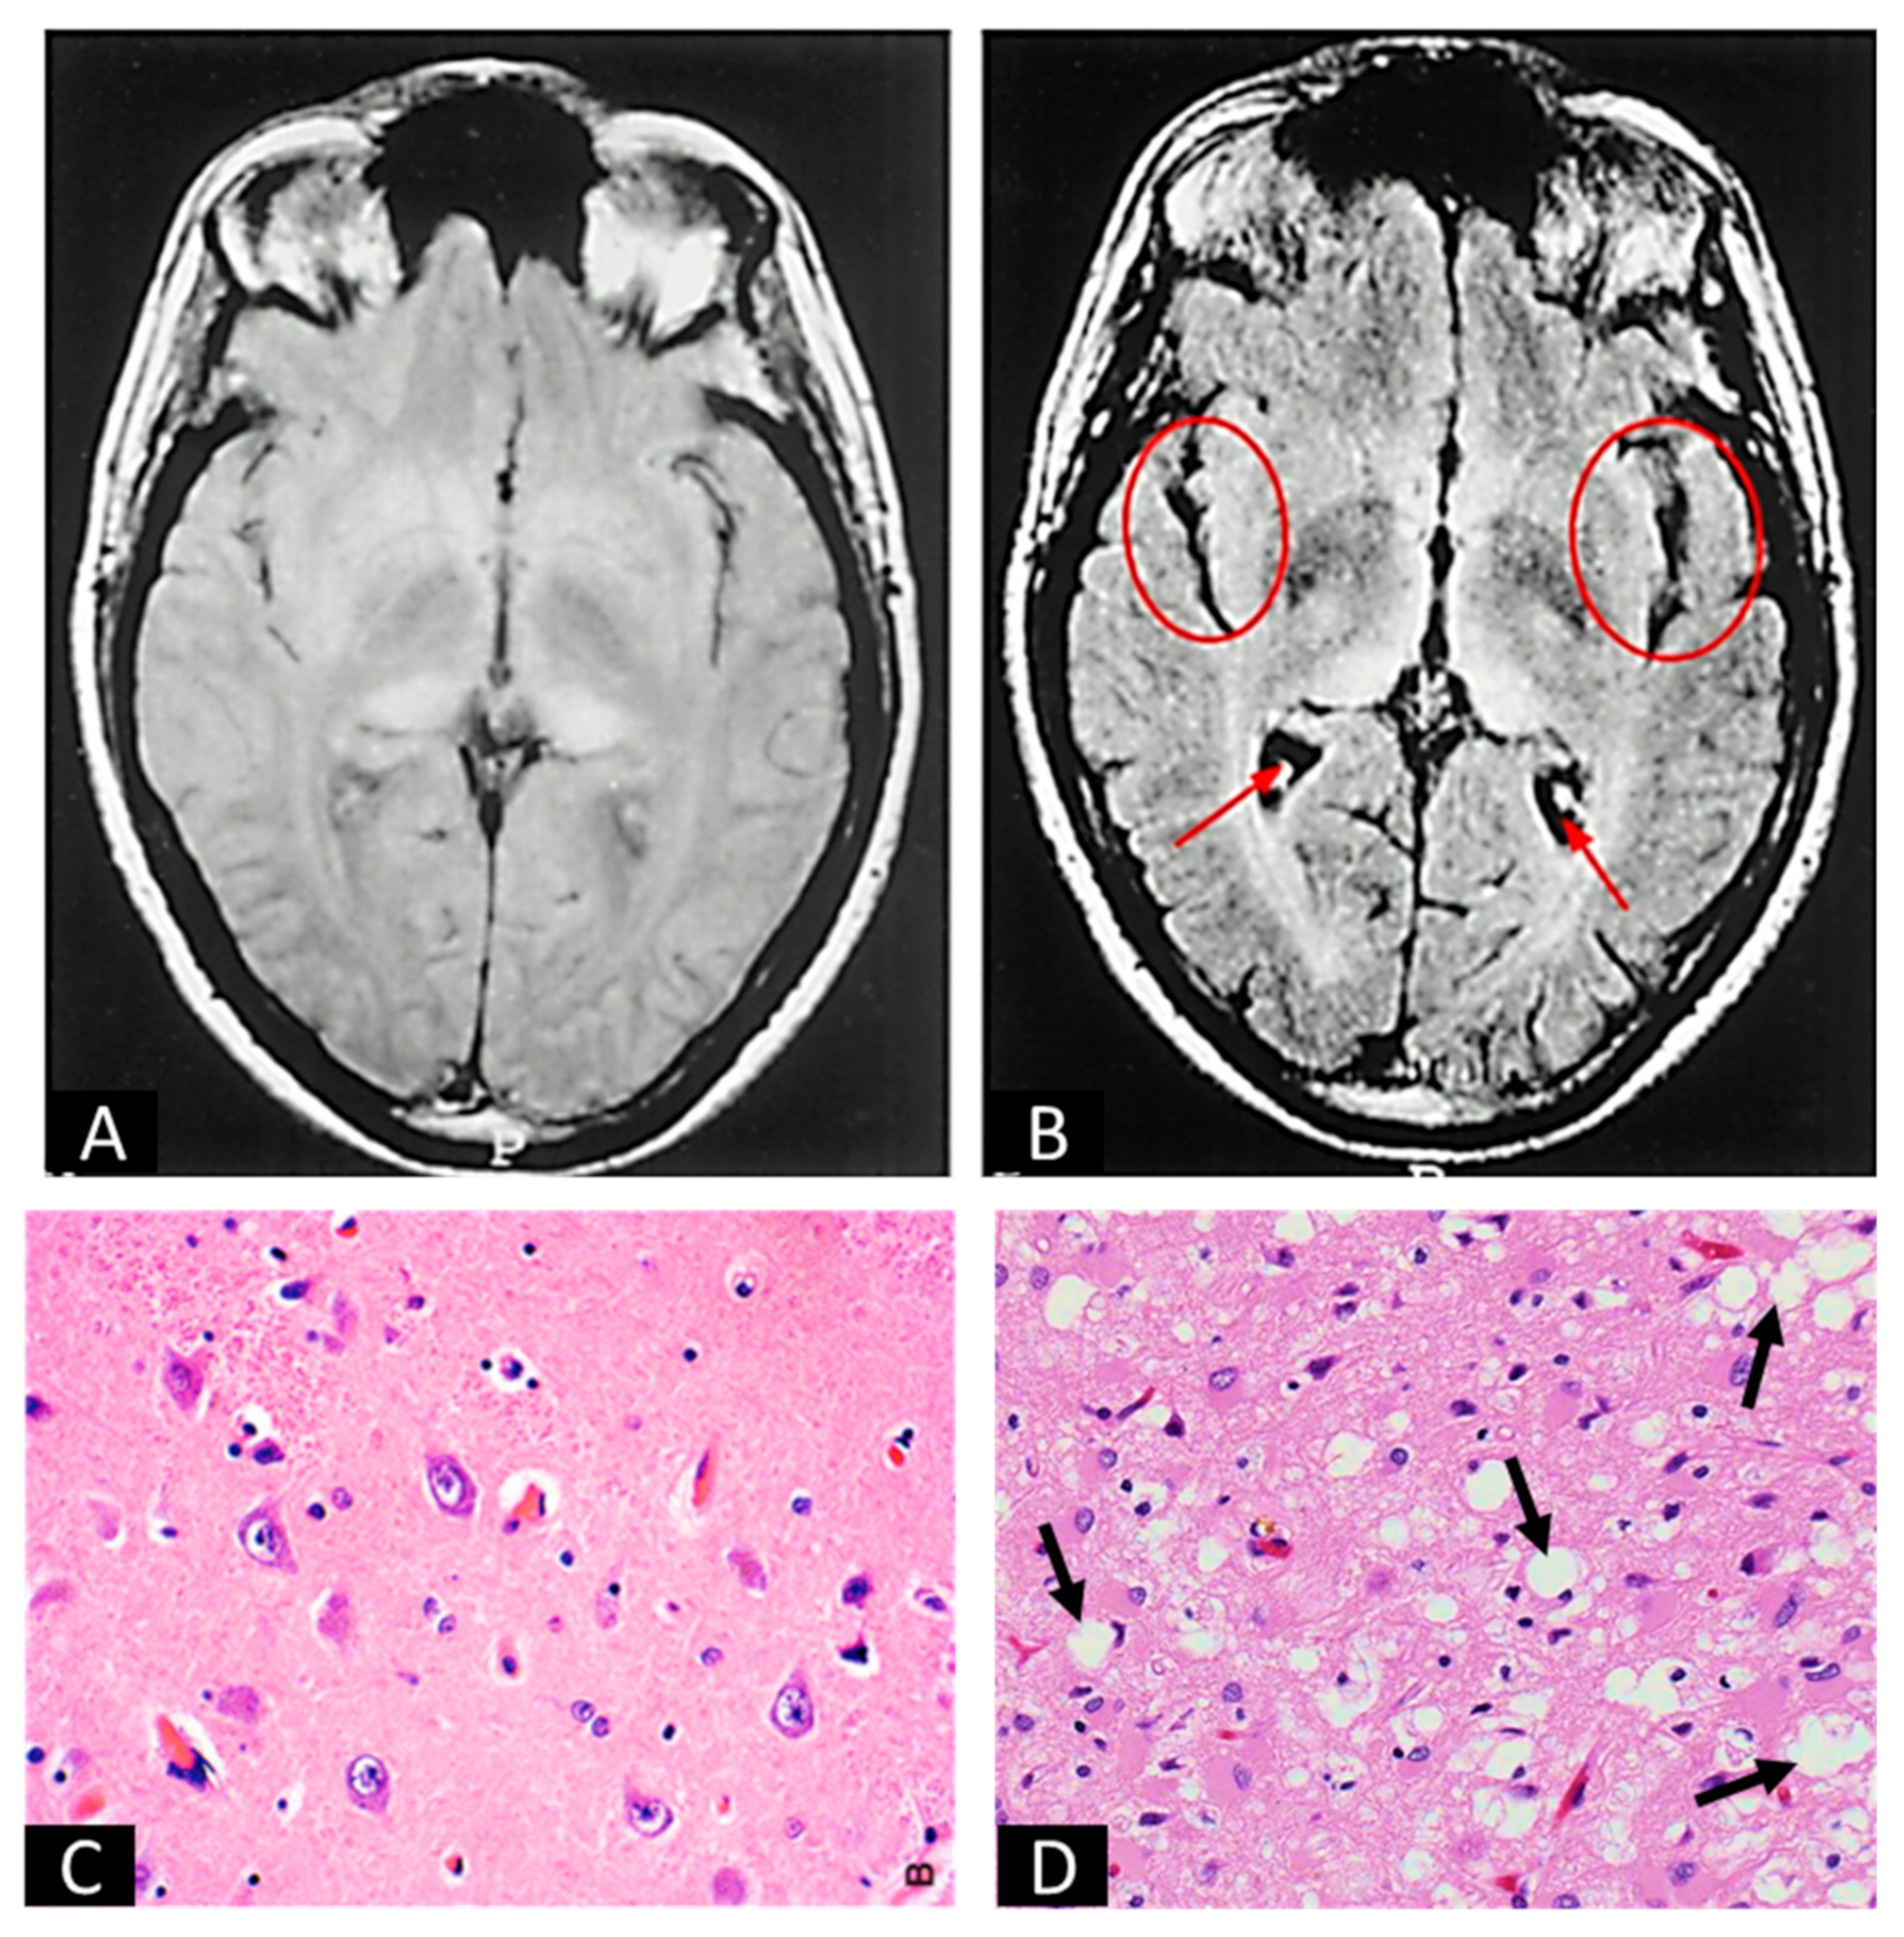

- Macfarlane, R.G.; Wroe, S.J.; Collinge, J.; Yousry, T.A.; Jäger, H.R. Neuroimaging findings in human prion disease. J. Neurol. Neurosurg. Psychiatry 2007, 78, 664–670. [Google Scholar] [CrossRef]

- Zeidler, M.; Collie, D.A.; Macleod, M.A.; Sellar, R.J.; Knight, R. FLAIR MRI in sporadic Creutzfeldt-Jakob disease. Neurology 2001, 56, 282. [Google Scholar] [CrossRef]

- Perry, A.; Bratt, D.J. Practical Surgical Neuropathology: A Diagnostic Approach, 2nd ed.; Pattern Recognition; Elsevier: Amsterdam, The Netherlands, 2018. [Google Scholar]